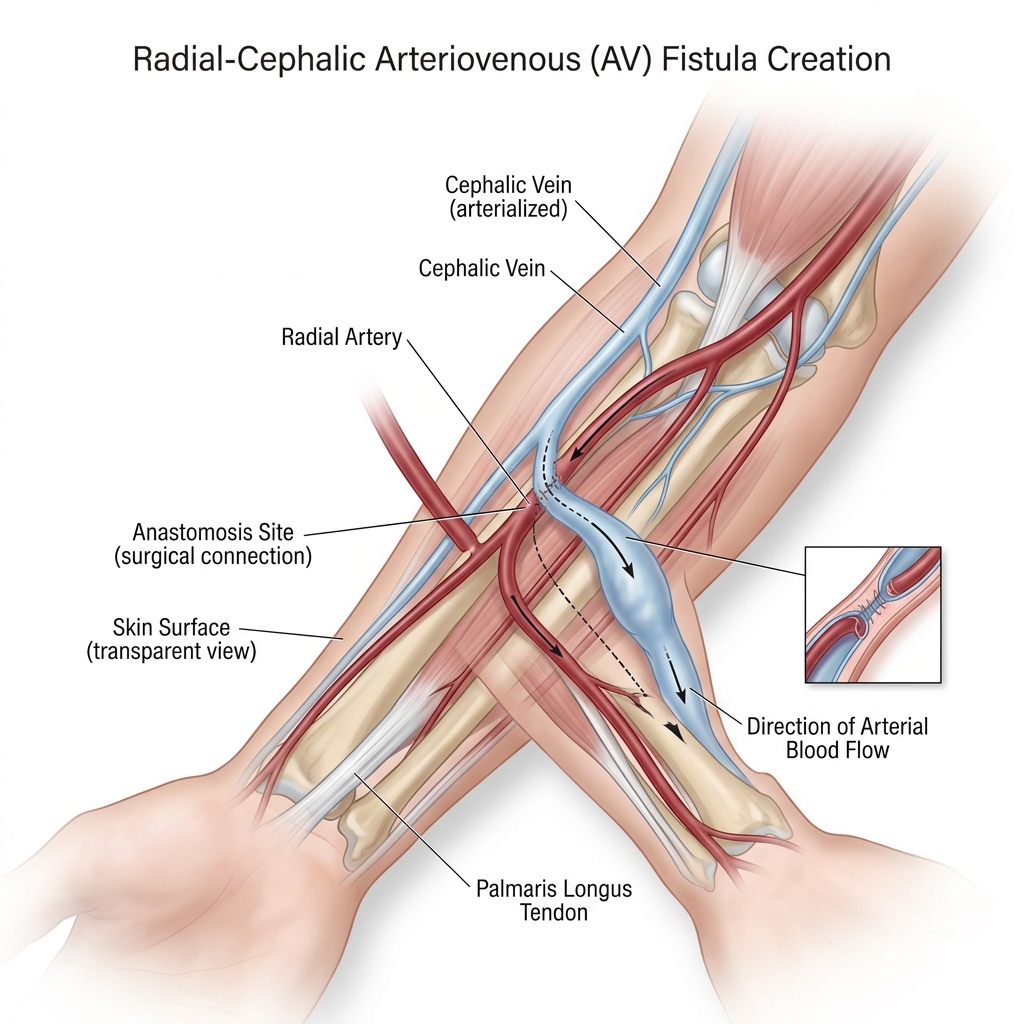

Novo serviço municipal amplia o acesso vascular definitivo para pacientes renais, reduzindo riscos.

Entenda por que a fístula é o acesso vascular padrão ouro, como funciona a cirurgia e quais os cuidados essenciais para sua durabilidade.